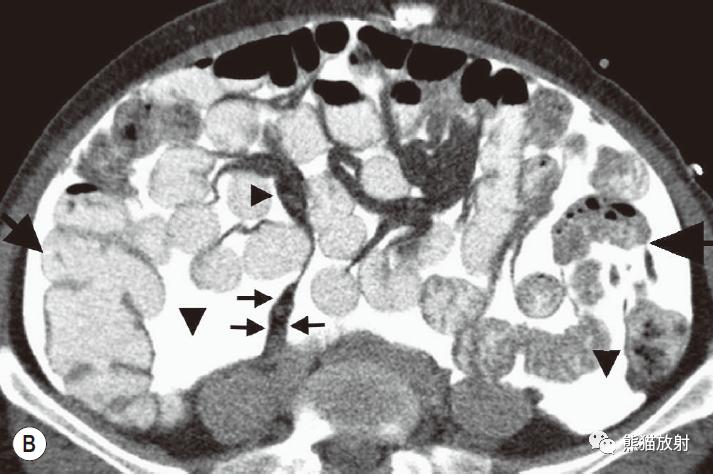

腹内疝:内脏通过腹膜或肠系膜孔突出形成。

包括:十二指肠旁(53%)、盲肠周围(13%)、Winslow孔(8%)、肠系膜和结肠系膜(8%)、乙状结肠间(6%)、吻合口后(5%)疝。

肠系膜疝。 扩张、充满液体的小肠襻丛位于前腹壁下的升结肠侧旁(箭),取代网膜脂肪。充盈的血管及邻近肠系膜模糊,反映了小肠绞窄性梗阻。